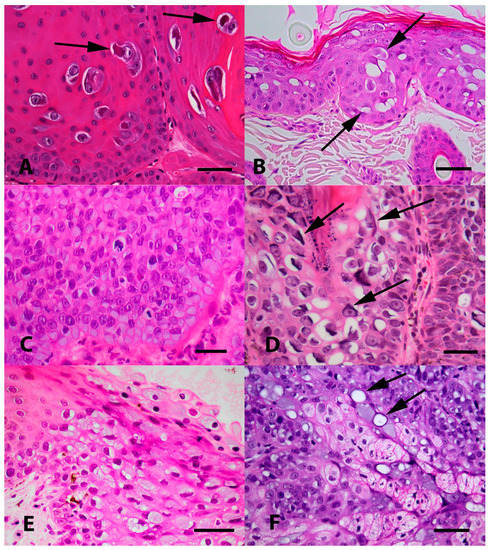

4.3. Feline Viral Plaques and Bowenoid In Situ Carcinomas

4.4. Feline Cutaneous Squamous Cell Carcinomas (SCCs)